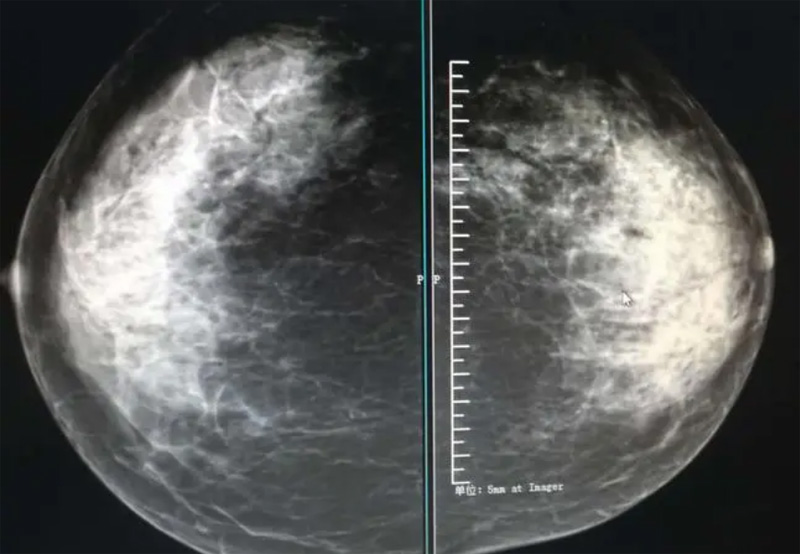

乳腺DR攝影體位有頭尾位及內外側斜位,

乳房在片子的中央,乳頭切線位,可見小部分胸大肌,內側乳腺組織應全部包括在片中,外側乳腺組織盡可能包括在片中。一張好的MLO位圖像顯示如下:乳房被推向前上,乳腺實質充分展開,胸大肌可見,較松弛,下緣達到乳頭水平,乳頭在切線位,部分腹壁包括在片中,但與下部乳腺分開,絕大部分乳腺實質顯示在片中。乳腺組織外緣可見乳頭的輪廓;乳腺后方的脂肪組織被很好地顯示出來,乳房無皺褶。對于CC位及MLO位顯示不良或未包全的乳腺實質,可以根據病灶位置的不同選擇以下體位:外內側位(LM)、內外側位(ML)、內側頭尾軸位(MCC)、外側頭尾軸位(LCC),尾葉位(CLEO)及乳溝位。在臨床實踐中,對于常規體位上發現的異常改變,可以進一步采取一些特殊的攝影技術,包括局部加壓攝影、放大攝影或局部加壓放大攝影技術。

2、規范觀圖程序:屏幕軟閱讀或在專用日光觀片燈下膠片閱讀,后者應同時準備白熾強光燈及觀片放大鏡。注意雙側乳腺配對觀察,推薦雙眼橫向掃描,進行雙乳相同部位圖像比較分析。

3、乳腺實質背景的確定:觀察乳腺實質與脂肪的構成比例,了解乳腺實質類型,以判斷對某些乳腺攝影征象敏感性的影響,有利于確定乳腺攝影對疾病的診斷價值。